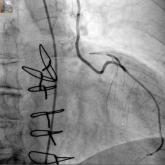

Hybrid revascularization shows promise, but there are concerns

Combined percutaneous procedures emerging in Europe